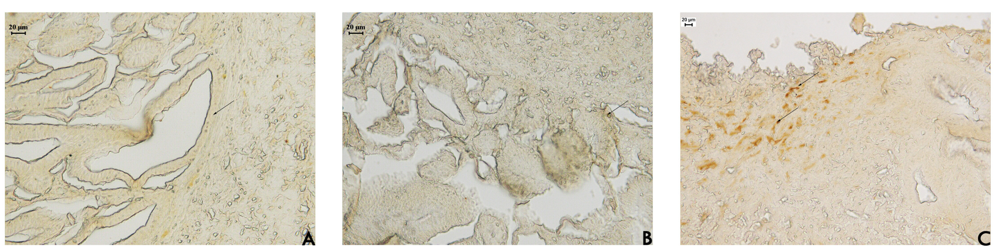

Our results (Table 3) show that EAF treatment increased the number of vessels in the ulcer margin compared to the other treatments, indicating that EAF stimulated angiogenesis in this regenerative area. Angiogenesis is essential for the healing of chronic gastroduodenal ulcers, and several new angiogenic factors have been identified in the gastric mucosa that play an organ-specific role in the formation of large blood vessels supplying the stomach and intestines [26,27]. This increased angiogenesis in the EAF group (Figure 4) explains why we observed increase in normal epithelial height and a reduction in regenerative epithelial height. The EAF treatment accelerated the cicatrisation process by increasing angiogenesis that contribute to an increase of the mucus barrier. This barrier plays an important role in the maintenance and renewal of the gastric mucosa epithelium.

In animal models of ulceration and gastrointestinal damage, COX-2 products actually promote gastrointestinal healing, and inhibition of COX-2 is required to produce acute gastrointestinal damage [30]. Guo et al. [31] showed that highly selective COX-2 inhibitors delayed ulcer healing impaired angiogenesis in rats. In this study, the expression of COX-2 was increased in gastric tissues obtained from rats in the EAF groups (Figure 5). A marked increase in COX-2 expression was found at the base of the ulcers. This result thus confirmed that COX-2 may play an essential role in the healing of gastric ulcers. Lima et al. [9] observed that EAF was able to increase PGE2 synthesis after acute treatment. Taken together, the action of EAF on COX-2 and PGE2 the gastric mucus barrier, cell proliferation and angiogenesis suggest that it might represent a new strategy of healing gastric ulcers.